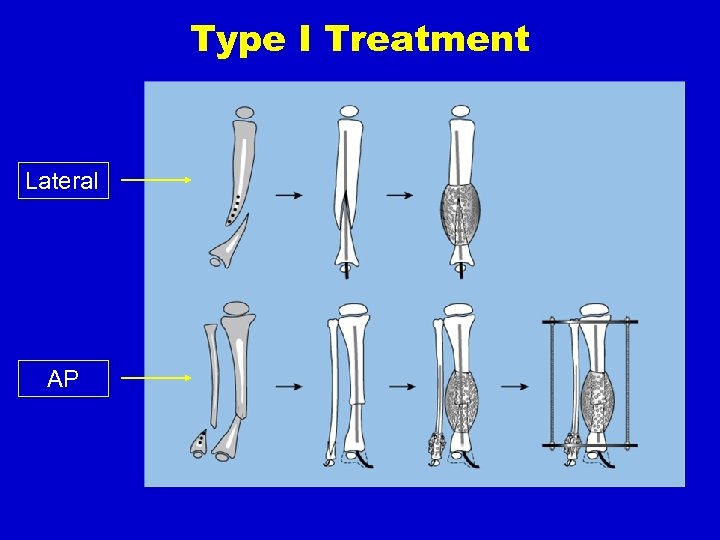

Type I Treatment Lateral AP